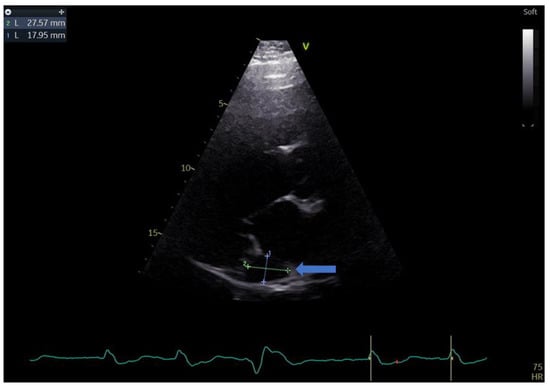

2. Case Report